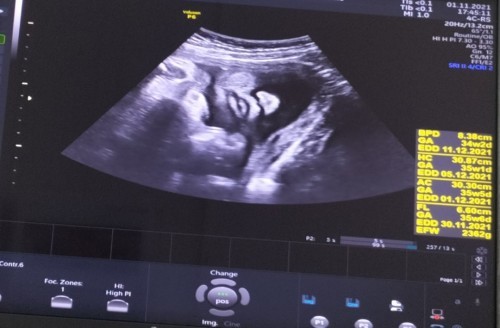

กำหนดคลอด เดือนธันวาคม ครับผมม.❤️

Post reply image